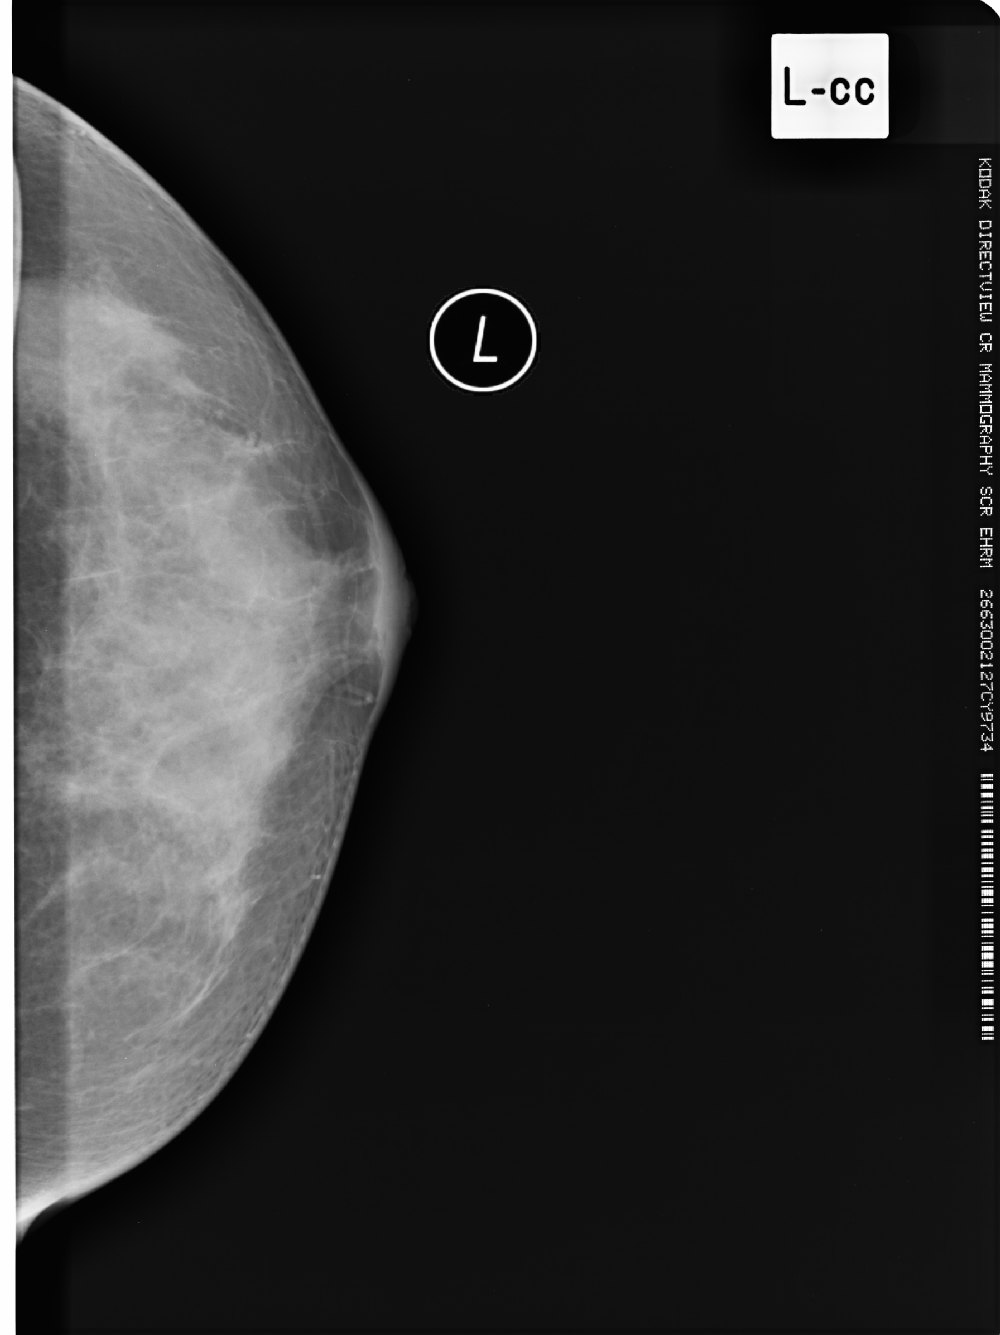

标题: X6857:女,39岁,右乳肿块半年余;三天后公布结果。 [打印本页]

标题: X6857:女,39岁,右乳肿块半年余;三天后公布结果。

左侧乳腺局部不对称性密度增高,局部可见纠集征象,左侧乳腺癌不除外。

所见乳腺内见斑片状高密度影,未见明显占位征象,考虑乳腺小叶增生,结合临床及b超。

左乳腺体增生可能性大

x6857,女,39岁,右乳肿块半年余;病理结果。

“右”乳纤维腺瘤

纤维腺瘤诊断要点:1,40y以下青年女性2,类圆形肿块,边光、锐利,可有分叶,密度或信号均匀,部分可见粗颗粒样钙化3,增强多呈缓慢渐近性直均匀强化或离心样强化。